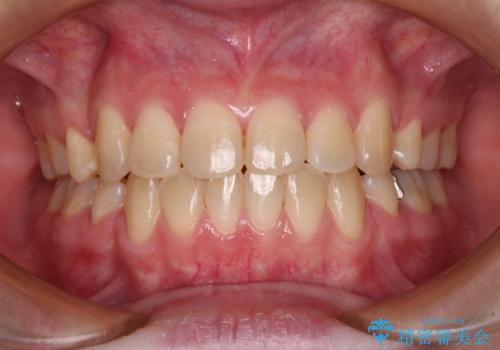

- 以前矯正治療を行ったものの、思い通りの仕上がりではなく、更には後戻りが気になってきたとのことで来院された患者様です。

上顎右側の第一小臼歯が動きにくい歯であり、以前矯正治療を行った際に傾斜した位置のまま終了したことと、それに伴い後戻りで歯列が波打っているようになっていることを大変気にしていらっしゃいました。

咬合平面改善のため、アンカースクリューを多用し、ワイヤー装置にて矯正治療を行うこととしました。